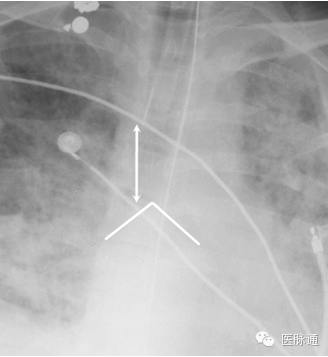

虽然支气管插管后,最初通过双肺听诊以及CO2监测确定插管位置,但仍需常规胸片进行确认。气管插管内嵌有不透X光的线条,以便确认位置。插管尖端应当在隆突(图16折线)上2-6 cm(双箭头)。插管尖端位于这一位置时,可以在颈部屈曲或伸展时仍保证通气充分。如果插管位置过深,则可能造成选择性单肺插管,导致对侧肺完全不张。

图16